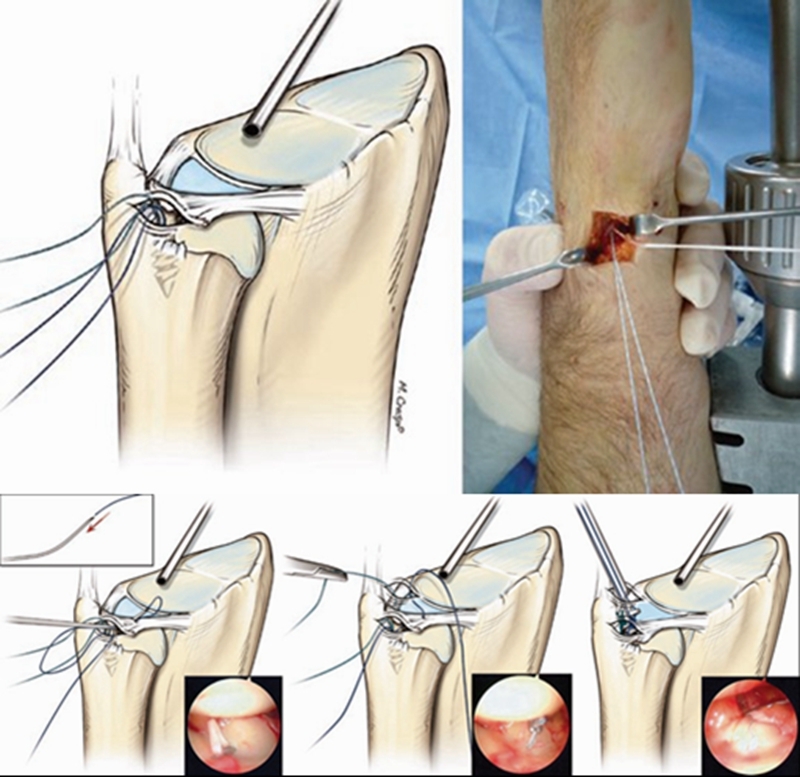

ⅠB型损伤手术治疗多采用缝合修复术。

TFCCⅡ型损伤,对症状持续存在,经保守治疗无效者可行腕关节镜手术。

ⅡA、ⅡB、Ⅱc型损伤:腕关节镜下清创术及软骨成形术;若合并尺骨撞击或尺骨正变异者,行关节镜下清创术结合尺骨头部分磨除术(Wafer术)。

Case1

女性,42岁,右腕疼痛1年+,2020年4月手术。

影像学检查

关节镜视频

关节镜下清理后